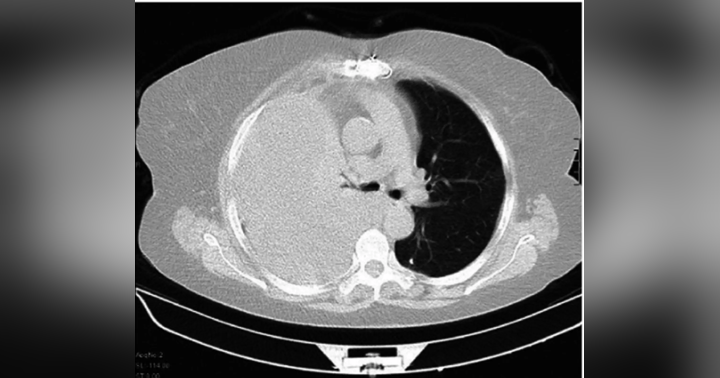

In this episode of Journal Club, Dr. Hassaballa discusses the recent study comparing small-bore to large-bore chest tubes for hemothorax drainage.